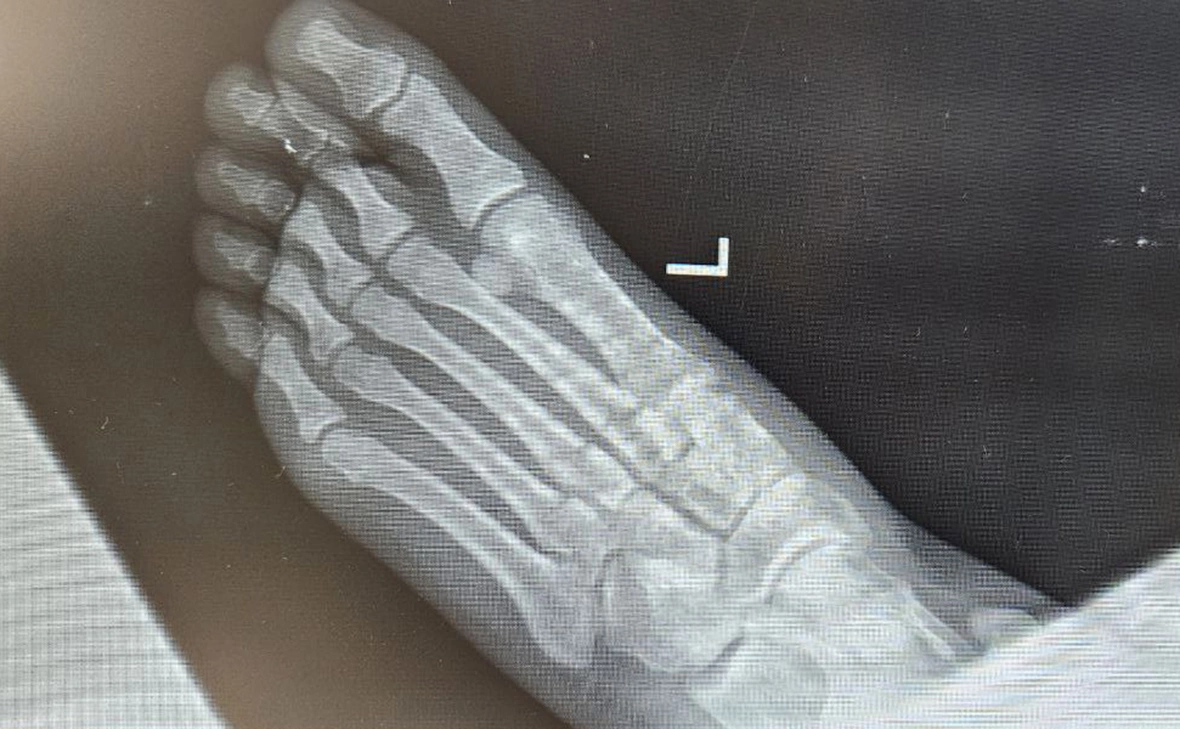

Старшей дочери художественного руководителя Большого Московского цирка Аскольда Запашного, Еве Запашной, диагностировали переломы трех костей стопы после внезапного падения лошади во время исполнения номера джигитов на лошадях в шоу «Легенда». Об этом сообщил Запашный в своем телеграм-канале.